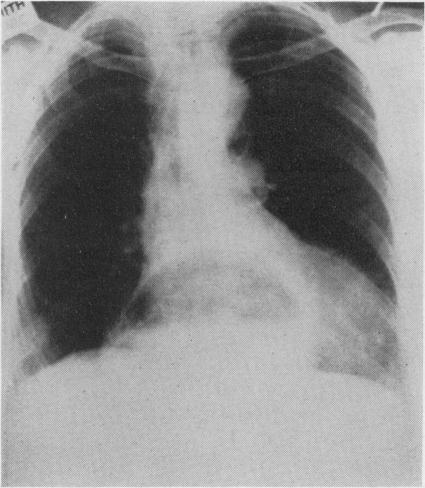

Hiatus hernia and Mallory-Weiss syndrome.

Postgrad Med J. 1967 Sep;43(503):609-11. doi: 10.1136/pgmj.43.503.609.